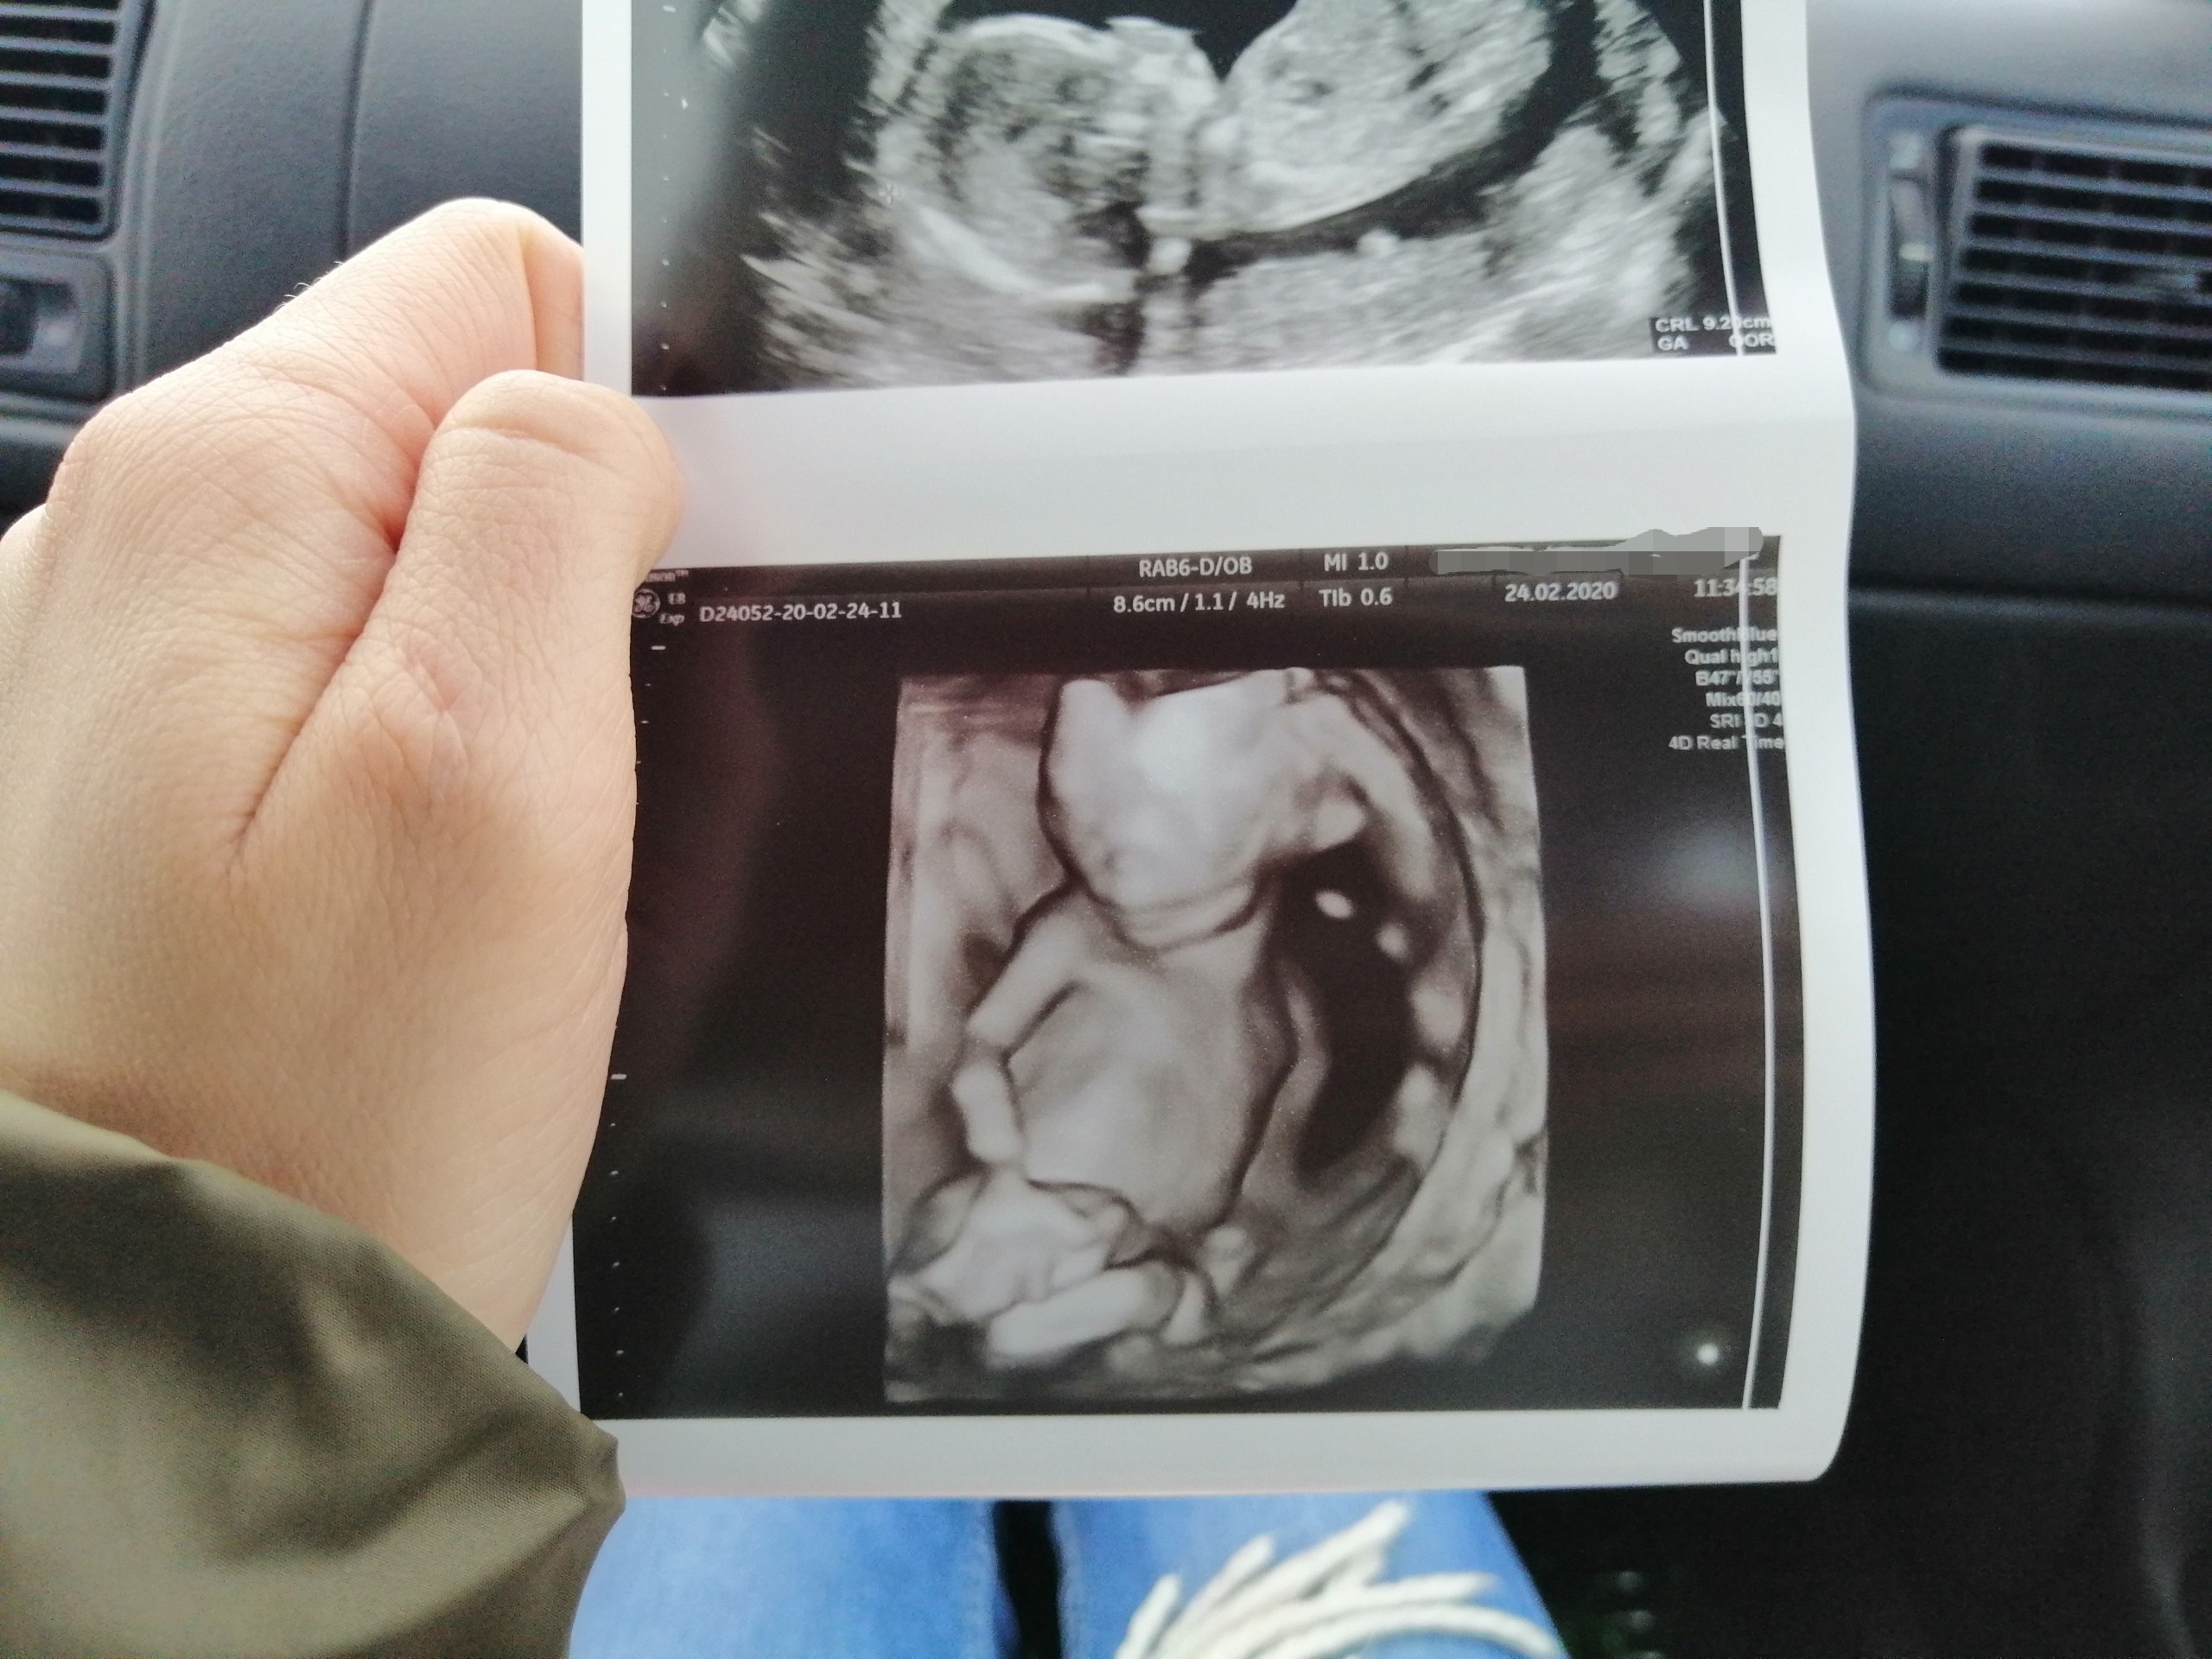

Cześć dziewczyny. Dawno mnie tu nie było, naprawdę dawno... :) U nas wszystko dobrze. Znacie już płeć swoich maluszków? U mnie na ostatniej wizycie 24.02 okazało się, że dziewczynka. Jestem taka szczęśliwa. W załączniku przesyłam moją damę trzymająca się za kolanko :D

Cześć dziewczyny. Dawno mnie tu nie było, naprawdę dawno... :) U nas wszystko dobrze. Znacie już płeć swoich maluszków? U mnie na ostatniej wizycie 24.02 okazało się, że dziewczynka. Jestem taka szczęśliwa. W załączniku przesyłam moją damę trzymająca się za kolanko :DZobacz załącznik 1085445